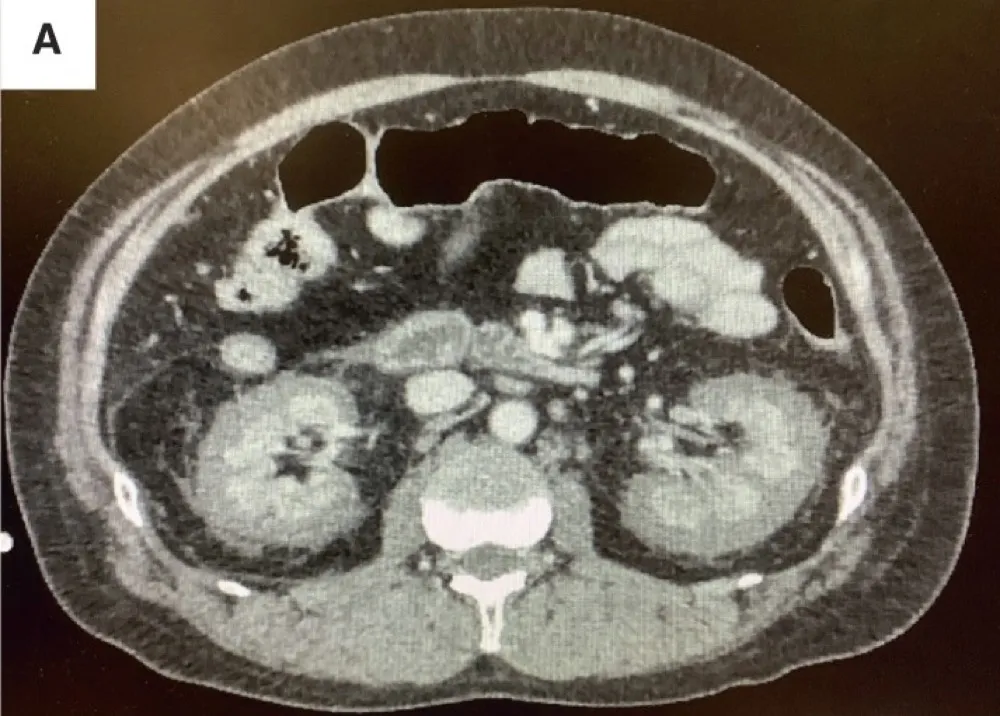

Necrose cortical renal, uma causa subdiagnosticada de IRA

Necrose cortical renal, uma causa subdiagnosticada de IRA

Frequentemente nos deparamos com pacientes que evoluem com quadro de IRA "desproporcional" ao quadro séptico, necrose cortical renal é uma entidade que não pode ser esquecida, principalmente em pacientes com complicações obstétricas